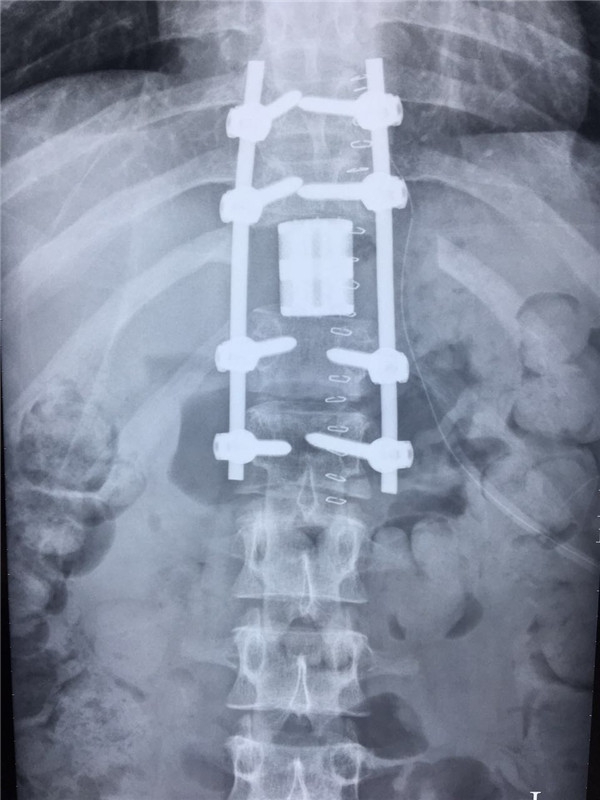

术后 正位

术后 侧位